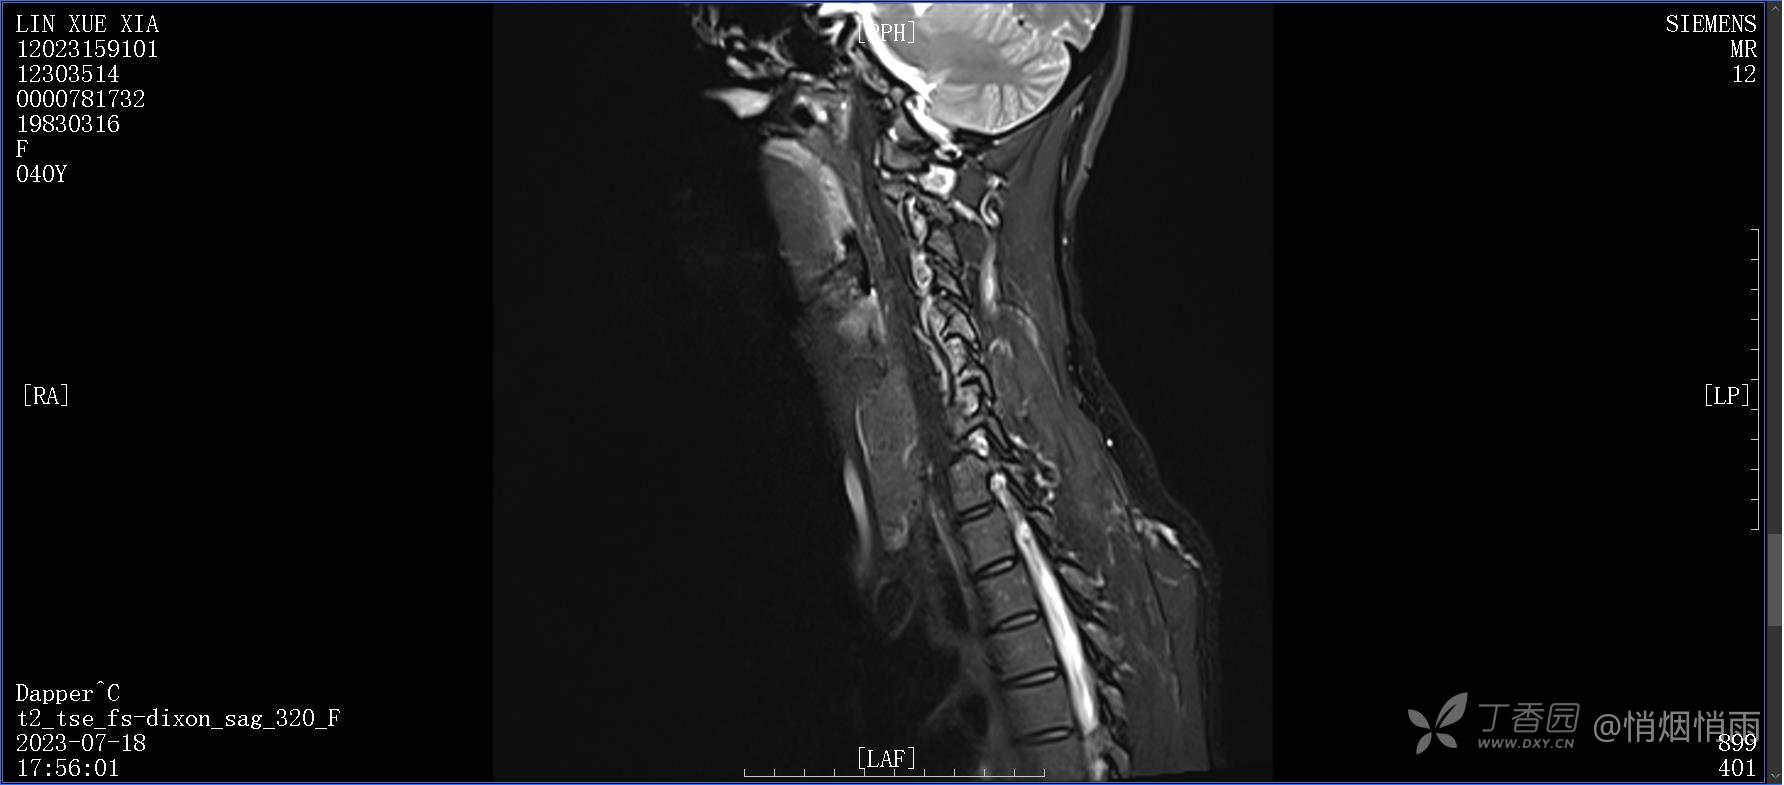

不明原因的右肩背部疼痛

NeurothinkerZ 推荐患者女性,40岁,因右肩背部疼痛班活动受限4日余入院(2023-07-17)。

病史:入院前4天无明显诱因突然感右肩背疼痛伴随活动受限,自行口服依托考昔、艾瑞昔布等药物治疗,院外应用肩关节局部手法按摩等,均无明显改善。外院门诊诊为颈椎病。自诉既往多次“胸椎小关节紊乱”于当地诊所行手法按摩,治疗后好转,否认慢性疾病病史、外伤史、手术史,诉青霉素过敏,无其他药物食物过敏史,否认吸烟史、饮酒史,月经正常,经量正常。

目前的诊断,暂时依据辅助检查诊为肩袖损伤,但是患者疼痛的性质和特点,却不是单纯的肩袖损伤所致。考虑过胸廓出口综合征,但是该疾病会出现肩胛区的疼痛吗?(由于考虑到费用的问题,没再进行下一步的检查)带状疱疹会有如此的症状吗?